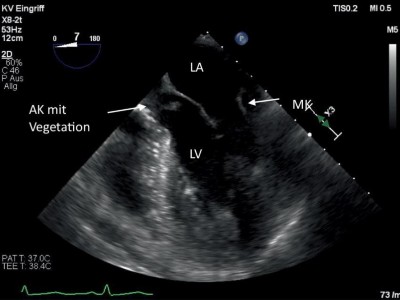

Fazialisparese und Endokarditis, aber Kultur negativ – was war die Ursache?

Bei blutkulturnegativen Endokarditiden kann die ergänzende molekulare Diagnostik der resezierten Herzklappe mittels eubakterieller PCR der entscheidende Faktor zur Identifizierung des Erregers sein. So auch im hier beschriebenen Fall eines 60-jährigen Mannes, der sich initial mit Fazialisparese und Dysarthrie vorstellte.

Transkatheter Aortenklappenimplantation (TAVI)/© Boonyakiatwattana W. et al. doi.org/10.1186/s12872-022-02576-y unter CC-BY 4.0, Echokardiografie der Aortenklappe/© Pitchy / stock.adobe.com, Schmerzende livide Areale am Bauch/© A. Frahnert, Aneurysma bei 2-monatigem Säugling mit Kawasaki-Syndrom/© Navidi et al. https://doi.org/10.1186/s13256-024-04987-1 unter CC-BY 4.0, Kanüle für Katheterbehandlung/© romaset / stock.adobe.com, Ärztin führt eine Nierenultraschalluntersuchung durch/© Graphicroyalty / stock.adobe.com (Symbolbild mit Fotomodell), Patient mit perforierter ICD-Tasche/© P. Fleckenstein, Vegetationen der Herzklappe/© Schönfeld L et al. / all rights reserved Springer Medizin Verlag GmbH, Echokardiografische Evaluation der Aortenklappeninsuffizienz/© Digitales Archiv der Uniklinik Köln, Explantierte Prothese nach Transkatheter-Aortenklappenimplantation/© Saha S et al. / all rights reserved Springer Medizin Verlag GmbH, Mitralklappe/© Springer Medizin, Hauteffloreszenzen der rechten Hand/© Marschner M et al. / all rights reserved Springer Medizin Verlag GmbH, Search Icon, Eine ältere Frau riecht an einem Basilikumblatt/© Halfpoint / Stock.adobe.com (Symbolbild mit Fotomodell), Ultraschall bei einem älteren Patienten/© Alex Potemkin / Getty Images / iStock (Symbolbild mit Fotomodellen), Person hält Tablette und Glas/© bilderstoeckchen / stock.adobe.com (Symbolbild mit Fotomodell), EKG befunden mit System - EKG Essential/© Springer Medizin Verlag GmbH